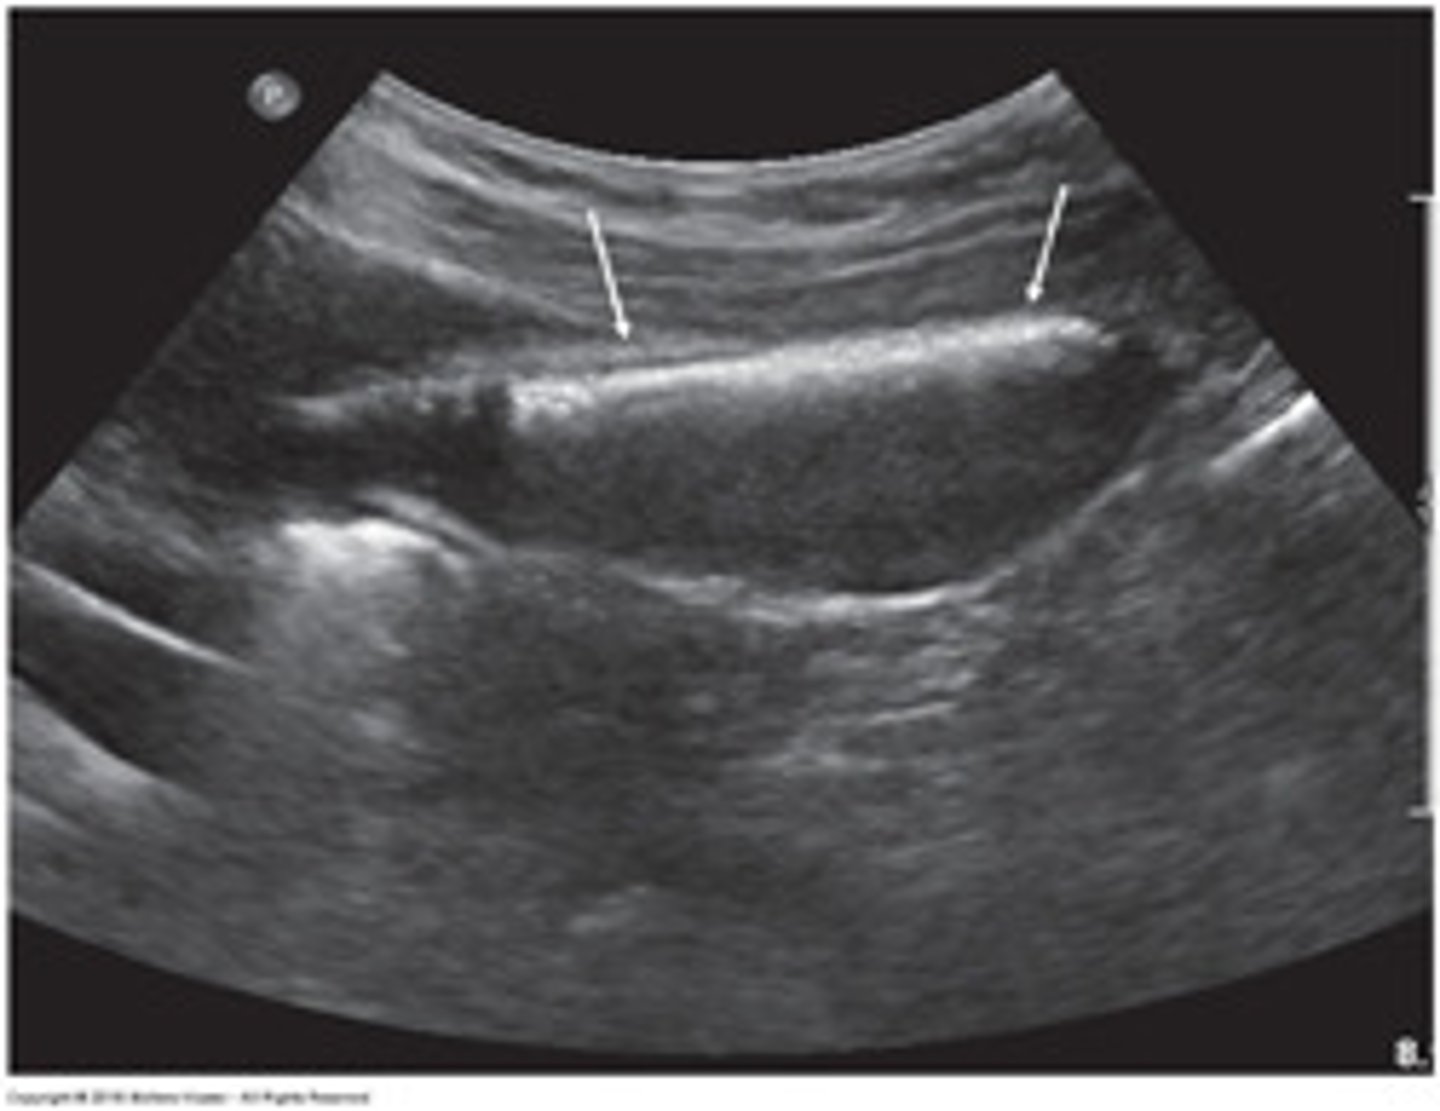

In the sagittal plane, the GB appears as an:

anechoic, pear-shaped structure located anterior to the right kidney and lateral to the head of the pancreas and duodenum

In the transverse plane, the GB appears as an:

anechoic and rounded

landmarks for identifying GB

Interlobar fissure/Main Lobar Fissure - appears as echogenic

linear structure connecting GB to MPV.